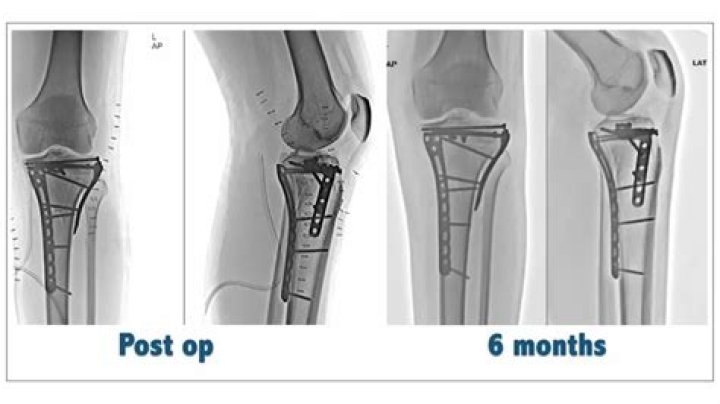

Open reduction and internal fixation (ORIF) is the mainstay of most tibial plateau fractures, with the aim to restore the joint surface congruence and ensure joint stability. Any metaphyseal gaps can be filled with bone graft or bone substitute.

Partially articular factures can be treated by minimally-invasive methods and arthroscopy is useful to assist and control the fracture reduction and to treat intra-articular soft-tissue injuries. Open reduction and internal fixation (ORIF) is the gold standard treatment for these fractures.